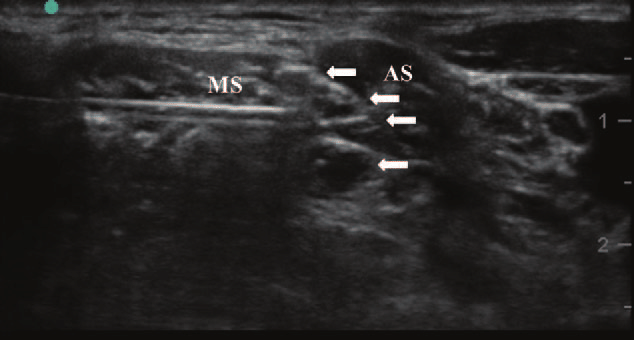

So when you are looking at 3-5 black circles in the interscalene groove, how do you differentiate which ones are C5, C6, C7 vs. multiples coming off the same root? For example how do we know in the picture below that we are not looking at C5, C6, C6, C7 (or any other anatomical variant).

Or do you simply inject tangential to the posterior border of the cluster of 3 "stoplights"?

So when you are looking at 3-5 black circles in the interscalene groove, how do you differentiate which ones are C5, C6, C7 vs. multiples coming off the same root? For example how do we know in the picture below that we are not looking at C5, C6, C6, C7 (or any other anatomical variant).

Or do you simply inject tangential to the posterior border of the cluster of 3 "stoplights"?